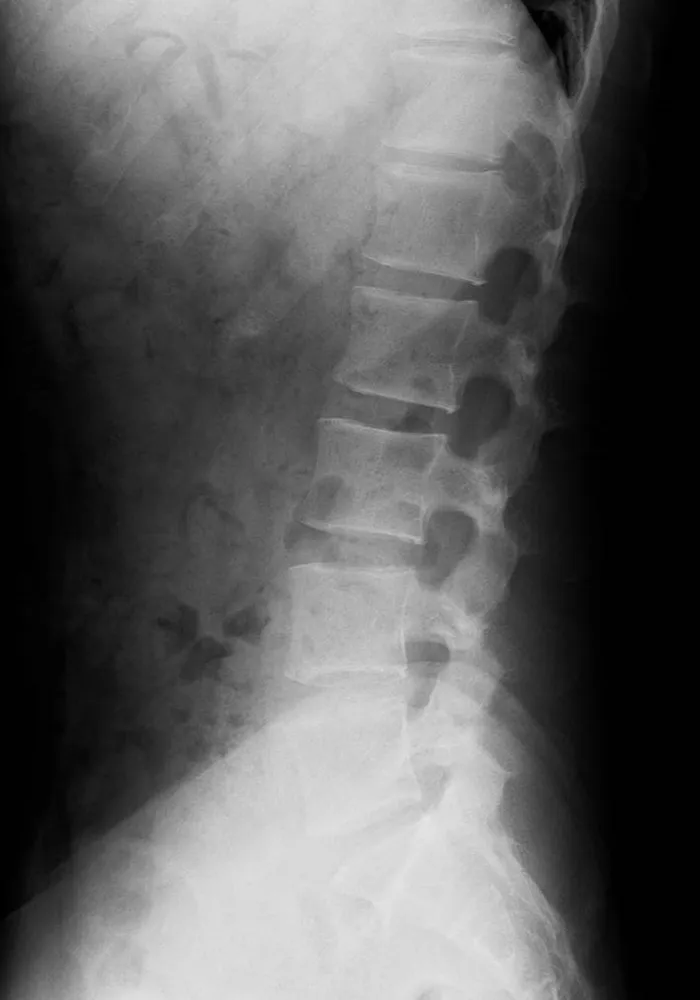

一般撮影は診断目的とする部分にX線を照射して撮影を行う検査です。X線は体内を通過する際に骨や筋肉、内臓などの組織により吸収される量が変化するので、透過したX線量の差を画像化したものがレントゲン写真となります。